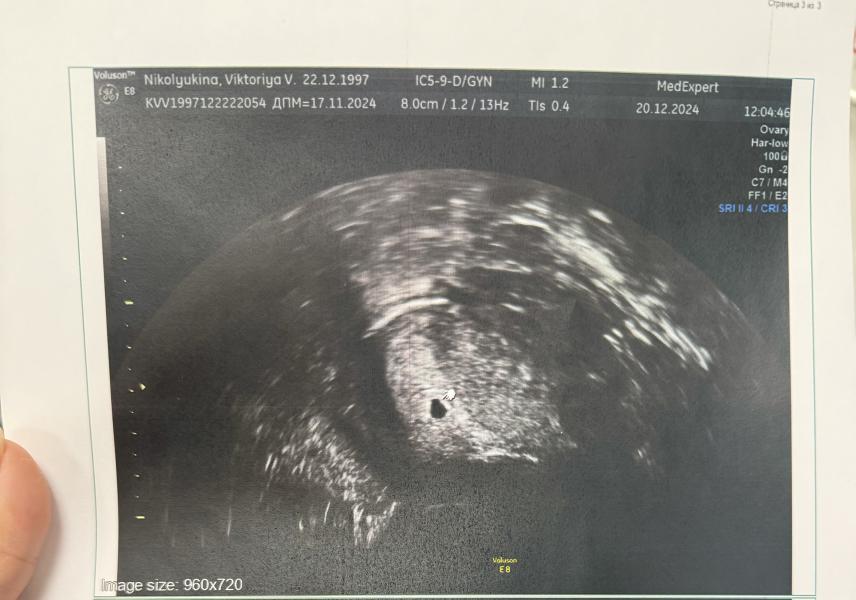

Соответствуем сроку, все хорошо, сказали, на 4,5 недель♥️♥️♥️

ПЯ - 4,1 мм🫶🏼🐣🙏🏼

Девочки, а то что желточного мешочка ещё нет это плохо??? А то что-то я запереживала

В следующий раз сказали приходить через 2 недели, но выдержу ли я столько ?? 😂